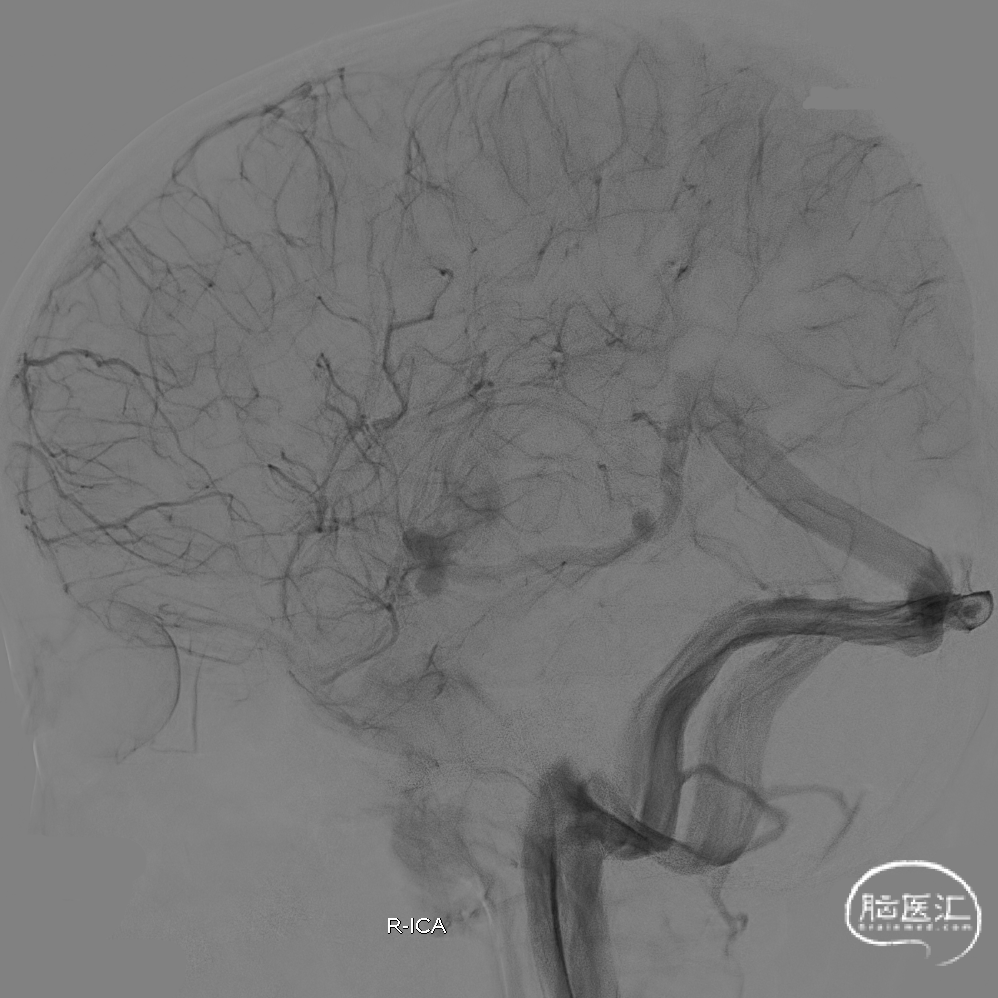

术后四月随访造影:

术后四月随访:

术后19月随访造影: